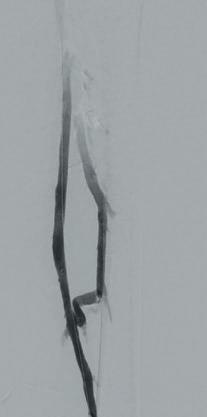

A 45-year-old man with a history of embolic and thrombotic events presented with left leg pain of one-week duration. The initial angiogram (Figure 1) showed new arterial thrombus in the mid to distal left SFA.

■ Thrombectomy

The Pounce system basket wire was deployed distal to the thrombus and the funnel catheter deployed proximal to the thrombus. The baskets were withdrawn into the funnel catheter and the system was removed, completing the first device pass. Balloon angioplasty was also performed to clear residual disease. The final angiogram showed full restoration of SFA flow (Figure 2)

■ Post-procedure outcome

The patient was discharged the next day. The Pounce system aided in the removal of acute and organized thrombus in one pass.

A male patient presented with immediate onset of numbness, pain and decreased function in his lower left leg. The initial angiogram showed complete thrombosis of the left popliteal, tibioperoneal trunk (TPT) and tibial arteries (Figure 1)

Two Pounce system passes removed organized thrombus from the popliteal artery, but distal flow continued to be hampered by an occlusion in the proximal anterior tibial (AT) artery. One pass with the Pounce LP System resulted in complete removal and resolution of the thrombus burden with improved flow through the AT to the plantar arch (Figure 2)

The patient was discharged after two days. The combination of Pounce and Pounce LP systems allowed for complete removal of organized thrombus from below-the-knee vessels without the need for thrombolytics or surgical intervention.